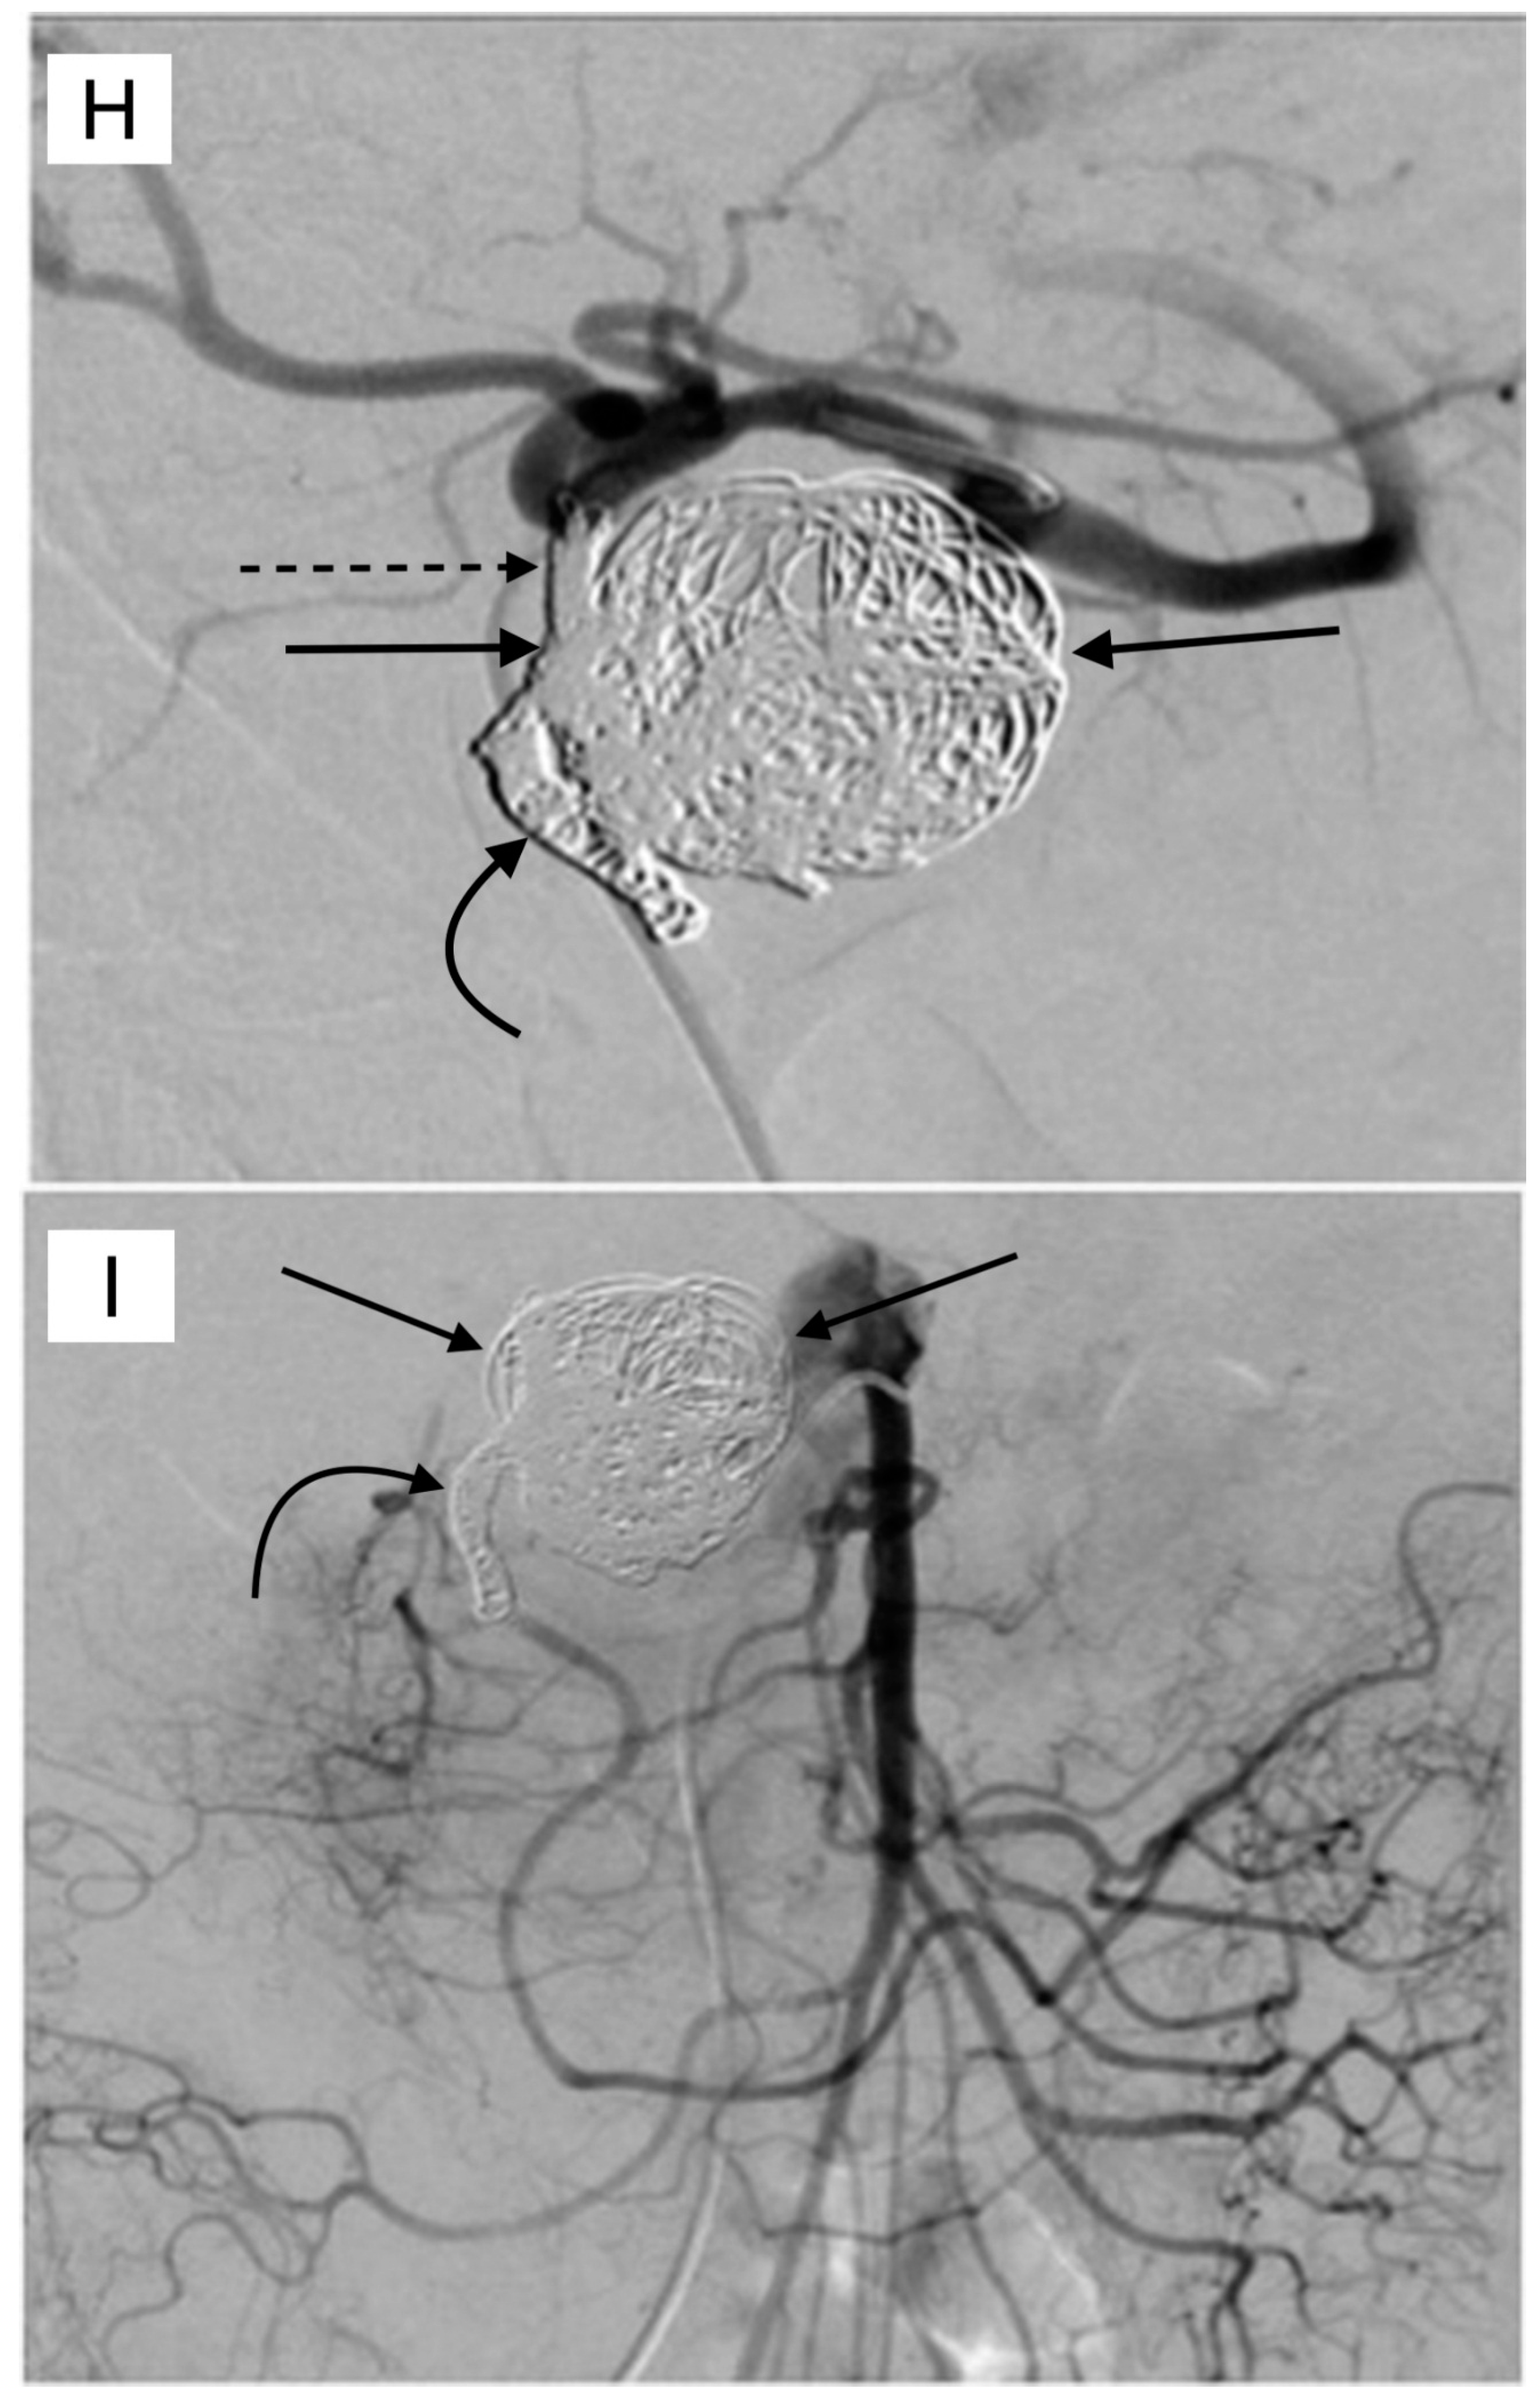

4. GDA Pseudoaneurysm Embolization